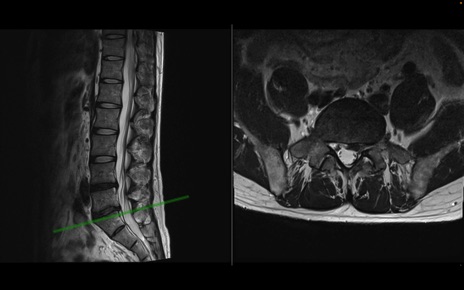

【整形】TIPS症例1 腰椎MRI 横断像と矢状断像

【症例】40歳代男性

【主訴】左臀部〜大腿後面痛み

【現病歴】2週間前から腰痛あり。2日前に夜中にくしゃみをした際に激痛が出現。疼痛強いため来院。

【身体所見】左臀部〜大腿後面、下腿後面のしびれ。SLR -/+ 30度、うつ伏せ困難、筋力低下なし。

異常所見と診断は?